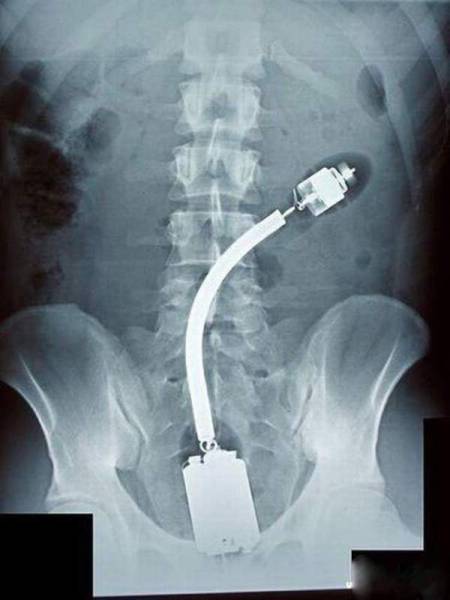

Lääkärit katsoivat nämä röntgenkuvat ja joutuivat hieraisemaan silmiään: 22 eksoottista kuvaa

Röntgenkuvat voivat paljastaa tärkeitä yksityiskohtia ihmisen terveydestä. Joskus ne havaitsevat kuitenkin myös asioita, joita ihmiskehon sisällä ei todellakaan kuuluisi olla.

Lääkärit saivat varmasti hieraista silmiään, kun he katselivat näitä röntgenkuvia. Toki joissakin tapauksissa tiedettiin jo, mitä etsiä, mutta osa tuli varmasti yllätyksenä.

Näiden kuvien jälkeen voin todeta, että olen nähnyt kaiken!